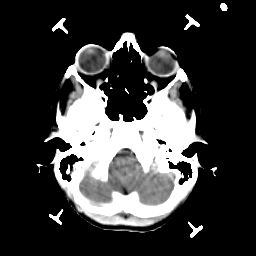

Metastatic bronchogenic carcinoma: Roentgen-ray CT -- Slice #3

[Home][Help][Clinical] Slice 3